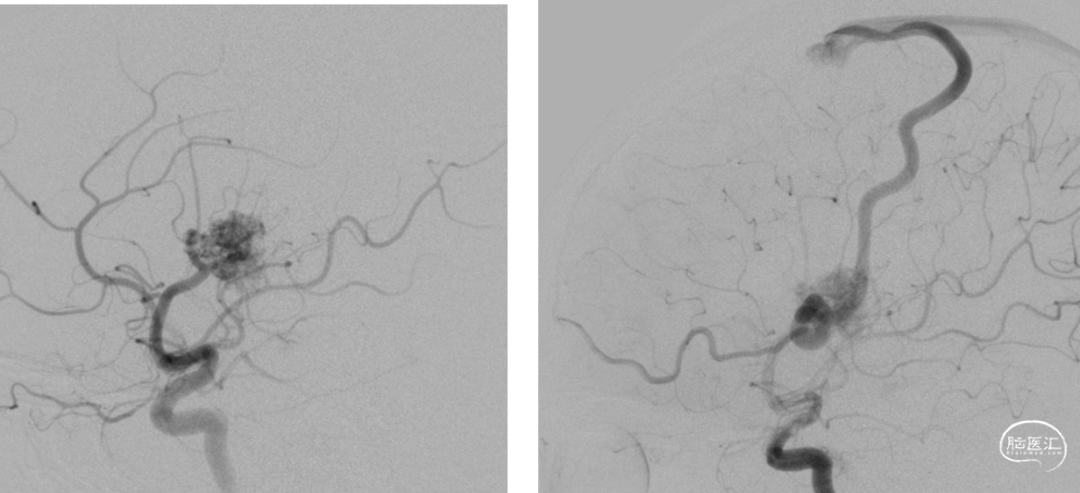

术前DSA

术中动脉造影

动静脉联合3d显示引流静脉与矢状窦关系;中天21微导管塑形(半圆)支撑下FATHOM-14导丝超选成功,考虑enchlon10长度不够,截断中管;FATHOM-14 3m交换enchelon10,但阻力大未能到位,中间管也未能到引流静脉入口;头羊作用下apollo3cm超选到位。

球囊保护静脉入路栓塞:注射onyx34约1ml,onyx18约1.5ml,总时长20min。

术后即刻造影畸形血管团不显影